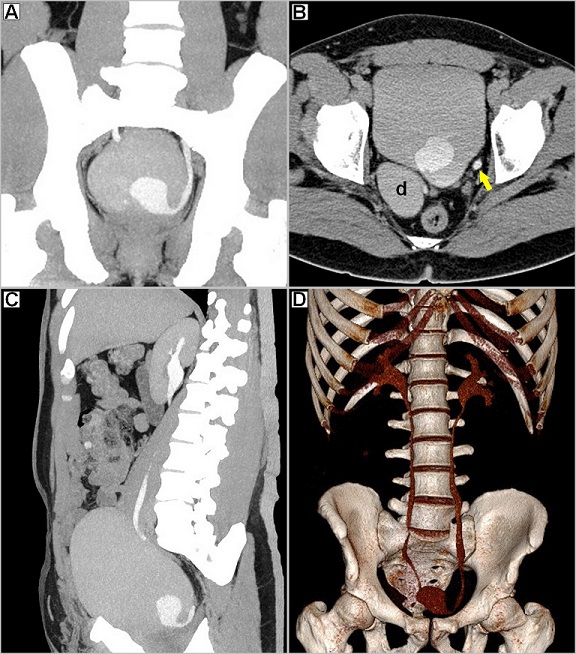

A 39-year-old man presented with complaints of long standing lower abdominal pain and episodic left renal colic, associated with urgency, frequency and dysuria. His physical exam, urinalysis and blood tests were unremarkable. Images from the contrast enhanced computed tomographic (CECT) scan of abdomen demonstrated the “cobra-head sign”(A,B), consistent with diagnosis of intravesical ureterocoele. Endoscopic incision of the ureterocoele was successfully performed and complete resolution of symptoms achieved. Ureterocoeles result from incomplete dissolution of the primitive membrane separating the ureteric bud from the developing urogenital sinus. Intravesical ureterocoele is defined as a cystic out-pouching of the distal ureter within the bladder, arising from a ureter with a normal insertion into the trigone-“orthotopic ureterocoele”. This type of ureterocoele is usually diagnosed in adults; hence, it is also called adult-type ureterocoele. Most intravesical ureterocoeles are incidental findings in asymptomatic adult patients, but may cause infections or calculi. Larger ones may cause bladder neck obstruction, along with obstruction of the ipsilateral ureter, which seems to have happened in our patient (B, C). However, he had neither hydronephrosis nor delay in the function of the left kidney (D). On contrast studies, they appear as a bulbous dilatation within the bladder, surrounded by a radiolucent halo-the 'cobra-head sign'. The lucent rim represents the combined thickness of the ureteral wall and prolapsed bladder mucosa, outlined by contrast material within bladder lumen. Also known as the “spring onion sign”, this cobra-head deformity is seen in only 50% of cases. It is important to distinguish ureterocoele (with thin and well defined lucent rim) from a pseudo-ureterocoele (with thick, irregular, or less well-defined lucent rim), as the latter can be caused by distal ureteric obstruction from a tumor or impacted calculus.